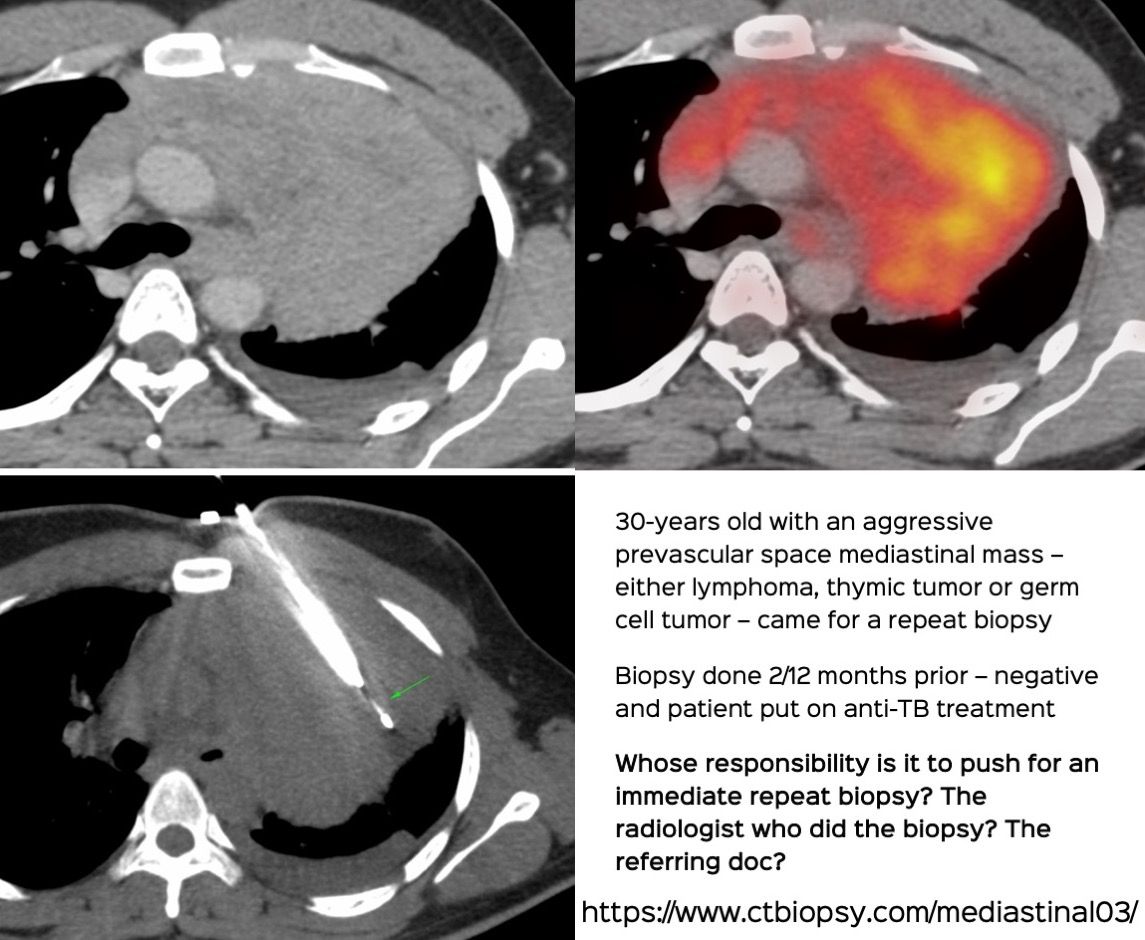

Case 69: Whose Responsibility is It After a Negative Biopsy to Push for a Repeat Biopsy?

Bhavin Jankharia - 03 December 2021